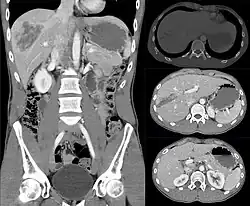

Isoliert_intraparenchymatoese_Leberruptur_24M_-_CT_KM_-_001

Imaging, such as the use of ultrasound or a computed tomography scan, is the generally preferred way of diagnosis as it is more accurate and is sensitive to bleeding, however; due to logistics this is not always possible.[6] For a person who is hemodynamically unstable a focused assessment with sonography for trauma (FAST) scan may take place which is used to find free floating fluid in the right upper quadrant and left lower quadrant of the abdomen. The FAST scan however may not be indicated in those who are obese and those with subcutaneous emphysema.[7] Its speed and sensitivity to injuries resulting in 400mL of free-floating fluid make it a valuable tool in the evaluation of unstable persons. Computed tomography is another diagnostic study which can be performed, but typically is only used in those who are hemodynamically stable.[7] A physical examination may be used but is typically inaccurate in blunt trauma, unlike in penetrating trauma where the trajectory the projectile took can be followed digitally.[8] A diagnostic peritoneal lavage (DPL) may also be utilized but has limited application as it is hard to determine the origin of the bleeding.[9] A diagnostic peritoneal lavage is generally discouraged when FAST is available as it is invasive and non-specific.[7]